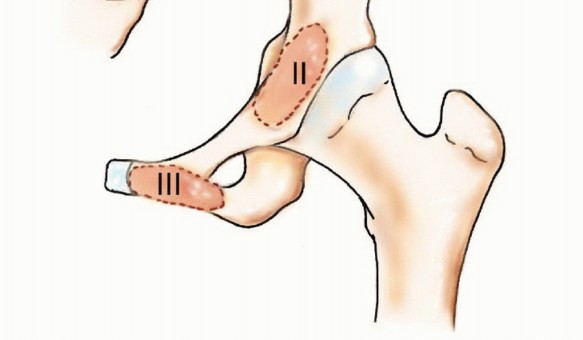

في بعض الأحيان، قد لا تؤثر هذه النقائل على استقرار ووظيفة الحوض بشكل مباشر، خاصة إذا كانت في مناطق مثل عظم الحرقفة أو العانة. ومع ذلك، فإن الأورام التي تصيب الجزء الخلفي من عظم الحرقفة قد تهدد سلامة المنطقة العجزية القطنية، بينما تلك التي تصيب التجويف الحقي (الحُق) يمكن أن تضعف بشكل كبير وظيفة مفصل الورك وقدرة الطرف السفلي على تحمل الوزن، مما يستدعي تدخلًا جراحيًا دقيقًا ومخططًا بعناية.

- تكوين مفصل الورك: يحتوي على التجويف الحقي (Acetabulum) الذي يستقبل رأس عظم الفخذ لتشكيل مفصل الورك، وهو مفصل محوري للحركة.

إن تعقيد تشريح الحوض، وتعدد الأوعية الدموية والأعصاب والأعضاء الحيوية التي تمر عبره أو تستقر فيه، يجعل جراحة نقائل الحوض من الإجراءات شديدة الدقة التي تتطلب جراحًا ذا خبرة استثنائية مثل الأستاذ الدكتور محمد هطيف. المناطق الأكثر عرضة للنقائل في الحوض تشمل عظم الحرقفة، التجويف الحقي، والعظم العجزي، وكل منها يتطلب نهجًا جراحيًا مخصصًا.